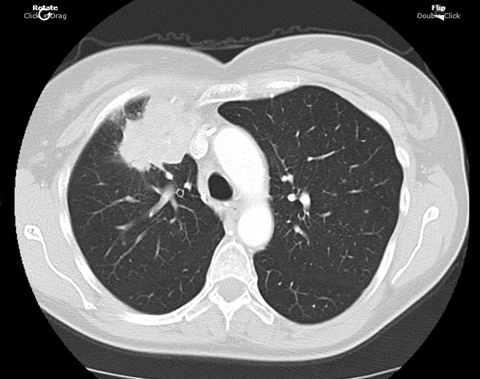

患者于2020年7月确诊为IV期(T3N2M1b)肺腺癌,具有KRAS G12C和STK11突变,且PD-L1表达阳性。基于患者的基因特征和免疫状态,治疗团队选择一线化疗联合免疫治疗方案,即卡铂、培美曲塞和帕博利珠单抗。在治疗初期,患者同时主动选择辅助治疗,并告知医生。患者主动参与治疗决策的这种行为,提示临床医生在制定治疗方案时,应充分考虑患者的意愿和对辅助治疗的需求。

cbf19472-0f0d-4fc8-b46e-daf06e7ba22f.png